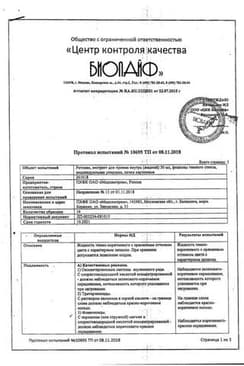

Сертификаты